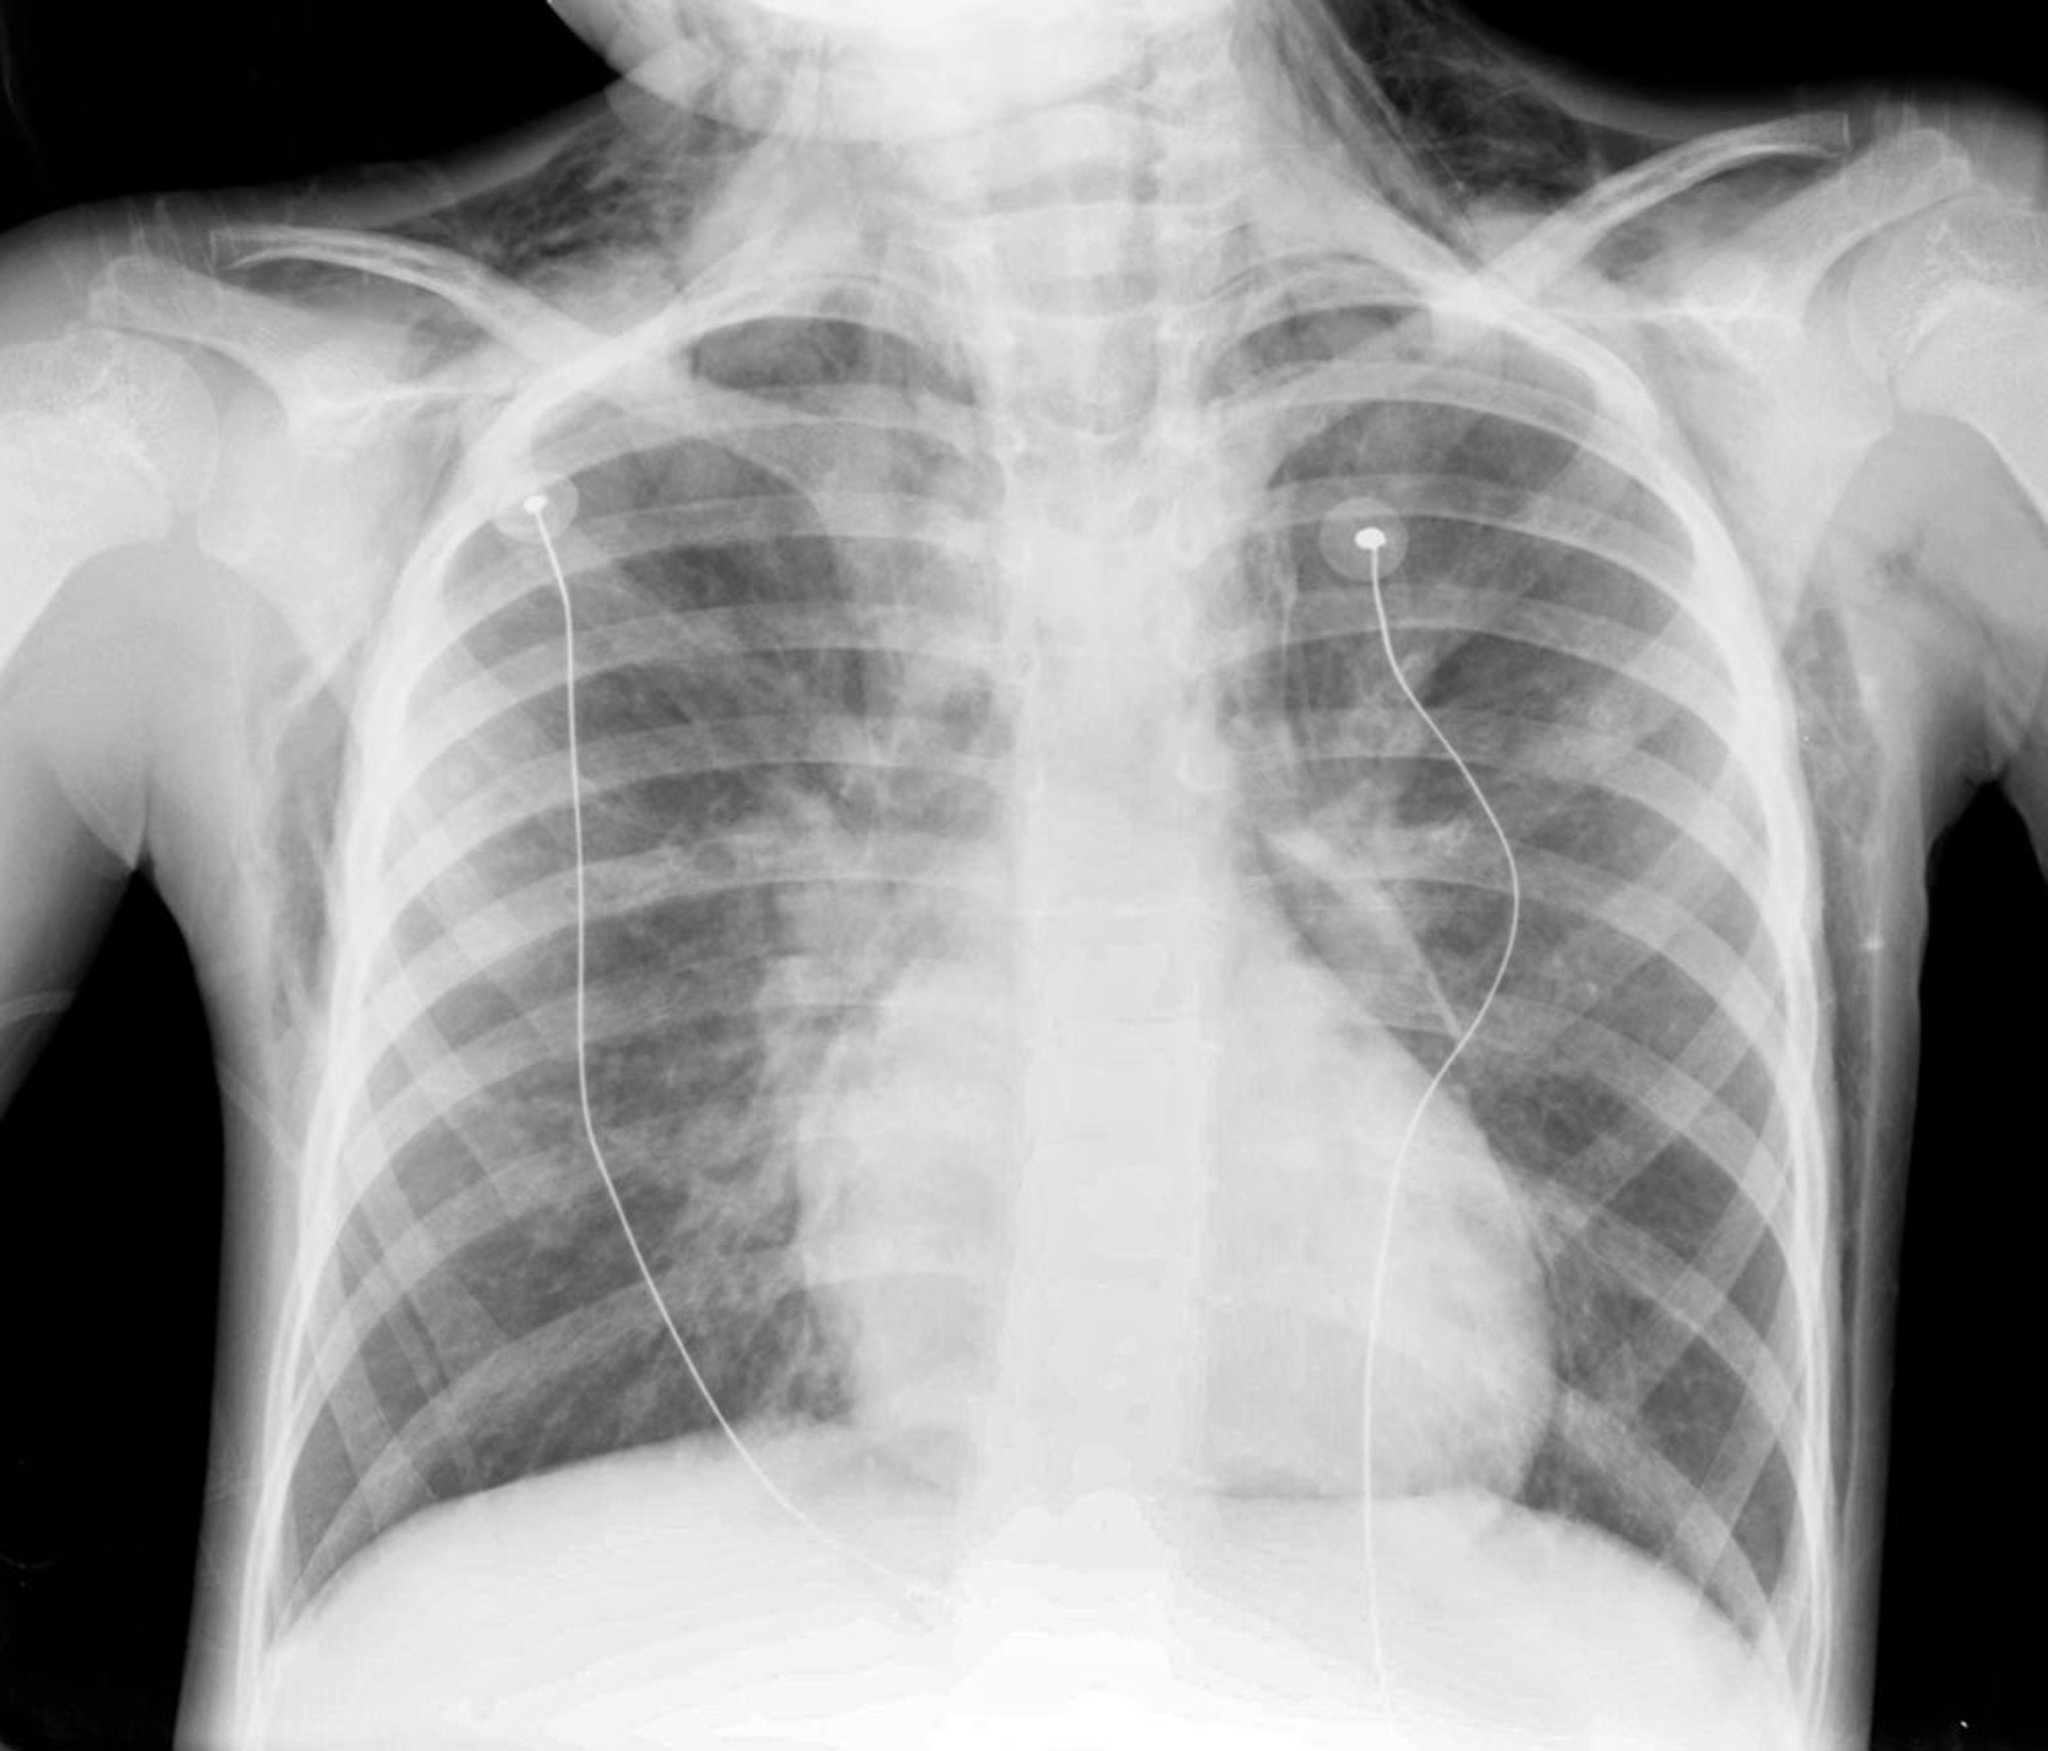

Neumomediastino (radiografía)

Esta radiografía muestra neumomediastino en un niño. Notése el aire alrededor del borde cardíaco y la tráquea, y en el cuello.